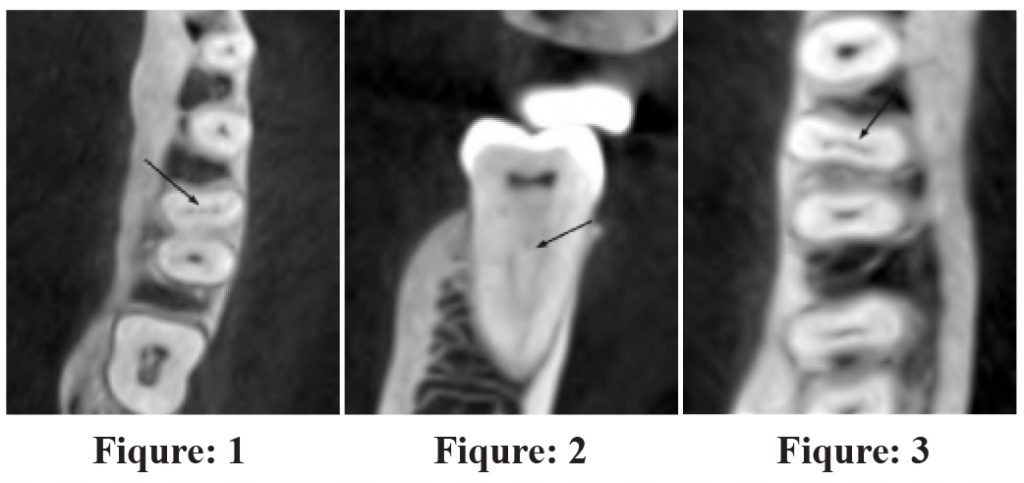

CBCTs of fifty one patients were evaluated (45% males and 55% females, mean age = 31 years). A total of one hundred and eighty-nine teeth were evaluated out of which ninety-four were mandibular first molars and ninety-five were mandibular second molars. MMC were found in nine (4.8%) teeth (Figure-1 & 2). In first molars, the prevalence

of MMC was 6.4%, while in second molars it was 3.2 %, P > 0.05 (Table-1). No significant difference was found when data was stratified for side, gender and age (Table-1). Isthmi were found in sixty-two (32.8%) teeth (Figure-3), with prevalence of 22.3% in first molar and 43.2% in second molar, P < 0.05 (Table-2). Significantly greater incidence of isthmi was found in younger age and in females, P < 0.05,